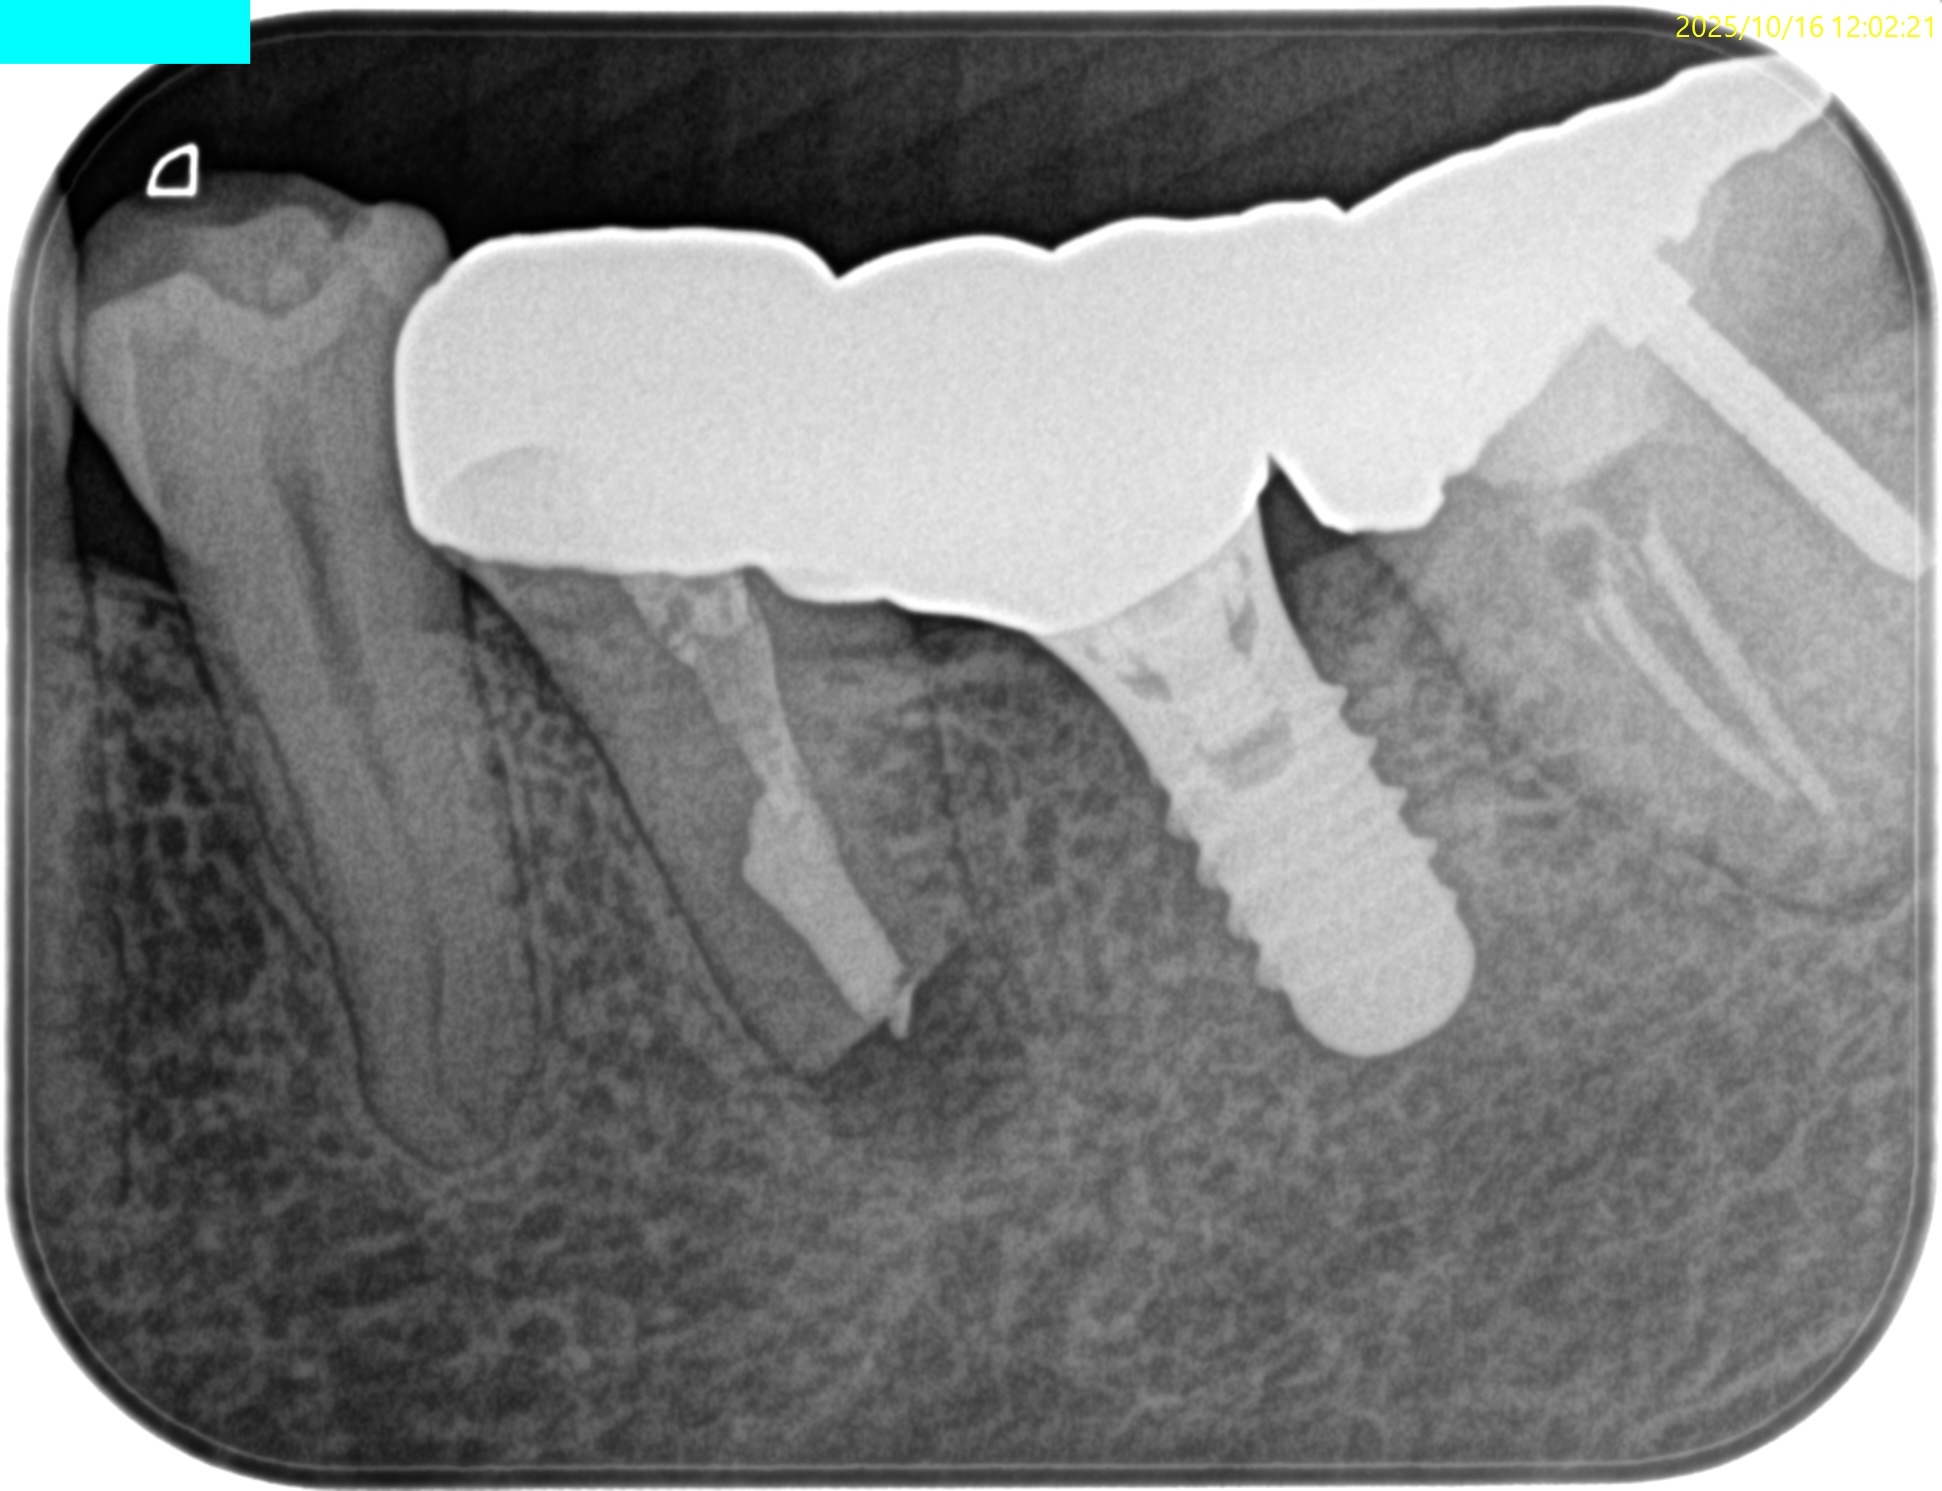

では、CBCTではどうだろうか?

そう。

Apicoectomyは不可能だ。

オトガイ孔を傷つけるリスクがあるからだ。

PAで状態確認し、問題がないことを確かめたのちに、

抜歯窩へ戻した。

術後のPA, CBCTは以下である。

問題はないだろう。